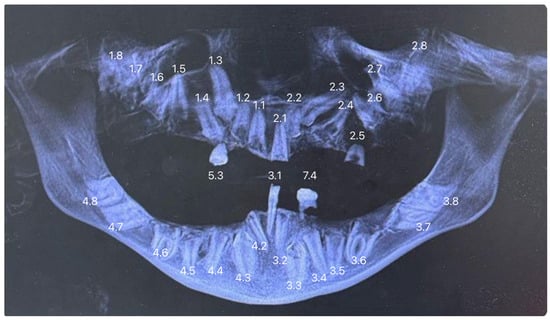

Extraoral examination revealed facial asymmetry, a dolichofacial growth pattern, and a concave facial profile (Figure 1a,b). As for the patient’s dental situation, intraoral clinical evaluation showed the presence of teeth 3.1, 5.3, and 7.4, along with a root remnant likely corresponding to 2.5 (Figure 2a,b,c,d,e). She showed a skeletal class III relationship due to the absence of erupted teeth. The patient’s mandible appeared prognathic, while the maxilla was severely hypoplastic [19,20]. The orthopantomography (OPG) revealed the presence of multiple impacted teeth, most of which exhibited abnormal morphology and incomplete development (Figure 3) [21]. The OPG was acquired using standard panoramic settings (66–70 kVp, 8–10 mA, exposure time 12–14 s) to obtain a comprehensive overview of dental development, impactions, and bone morphology. CBCT imaging was performed using a small-to-medium field of view (FOV 8 × 8 cm), 90 kVp, 5 mA, and a voxel size of 0.2 mm, allowing detailed assessment of tooth morphology, root development, and three-dimensional spatial relationships essential for treatment planning. Cone-beam computed tomography (CBCT) confirmed the findings and aided in treatment planning (Figure 4) [22]. Clinical photographs and radiographic records were collected, and the patient was enrolled in a multidisciplinary dental and prosthetic rehabilitation program.

Figure 3. Orthopantomography (OPG). The OPG image confirms multiple impacted permanent teeth throughout both the upper and lower arches, with abnormal morphology and incomplete root development of the retained elements.

3. Results

Despite the patient’s age of 24 years, the observed clinical features were consistent with a diagnosis of Infantile Refsum Disease (IRD). Clinically, the patient presented with a severe state of near-complete edentulism, with only the permanent incisor 3.1 and the retained deciduous teeth 5.3 and 7.4 present in the oral cavity. Skeletally, the patient exhibited a Class III relationship characterized by severe maxillary hypoplasia and mandibular prognathism (Figure 1a,b). The distinguishing aspect of the present case was the patient’s longevity and the unique radiographic finding of multiple impacted permanent teeth (including elements 1.1–1.8, 2.1–2.4, 2.6–2.8, 3.2–3.8, and 4.2–4.8) and near-complete edentulism—a combination not previously reported in association with this disorder (Figure 5). The patient was referred to a multidisciplinary prosthetic rehabilitation program.

Figure 5. The Orthopantomography (OPG) image displays the patient’s dentition with numerical labeling of the dental elements, using the standard FDI (Fédération Dentaire Internationale) system.

3.2. Radiographic Findings

Orthopantomography (OPG) and Cone-Beam Computed Tomography (CBCT) confirmed significant dental anomalies. The majority of the permanent dentition was impacted, including all permanent elements from 1.1 to 1.8, 2.1 to 2.4 and 2.8 (maxilla), 3.2 to 3.8, and 4.2 to 4.8 (mandible). Most of these impacted teeth exhibited abnormal morphology and incomplete development. Element 4.1 was absent due to prior extraction for advanced tooth decay at age 11. Such a severe pattern of dental impaction and tooth loss resulted in the observed near-complete edentulism, a finding that severely impaired oral function.